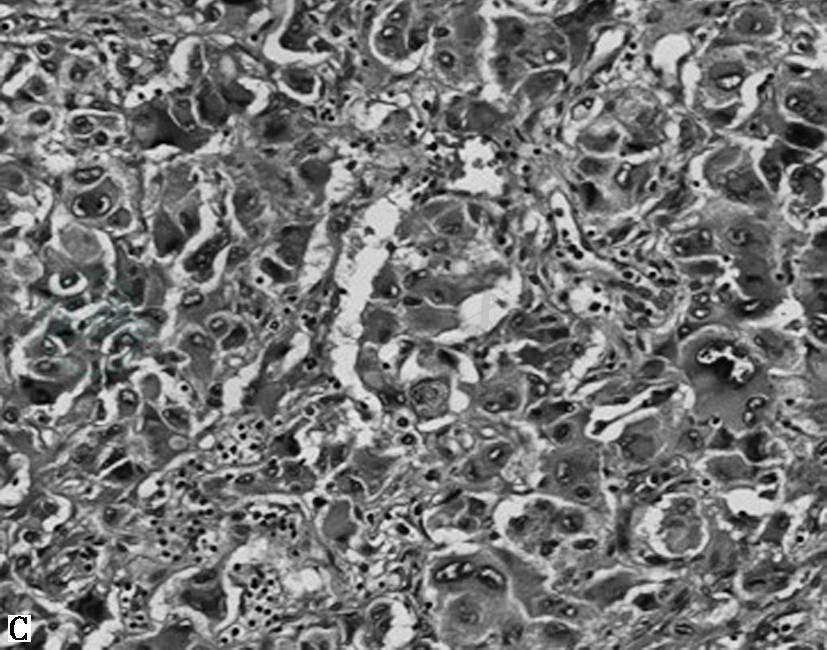

图1嗜铬细胞瘤镜下表现

A.HE 60倍,肿瘤周围见受压的肾上腺皮质;B.HE 100倍,特征性巢状(Zellballen结构),周围包绕纤细的纤维血管性间质;C.HE 200倍,肿瘤细胞形状和大小变化大,嗜碱性或嗜双色性,核仁明显,可见细胞核假包涵体及胞质玻璃样小体;D.HE 200倍,肿瘤细胞多形性及核深染明显,可见胞质内透明小球